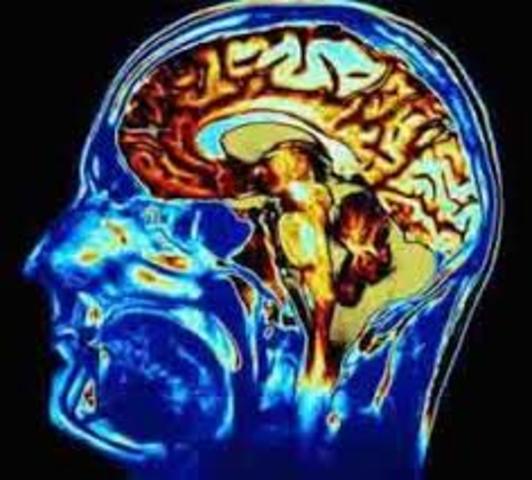

Rufus of Ephesus believed that the nervous system was instrumental in voluntary movement and sensation. He discovered the optic chiasma by anatomical studies of the brain. He stressed taking a history of both physical and mental disorders. He gave a detailed account of melancholia, and was quoted by Galen